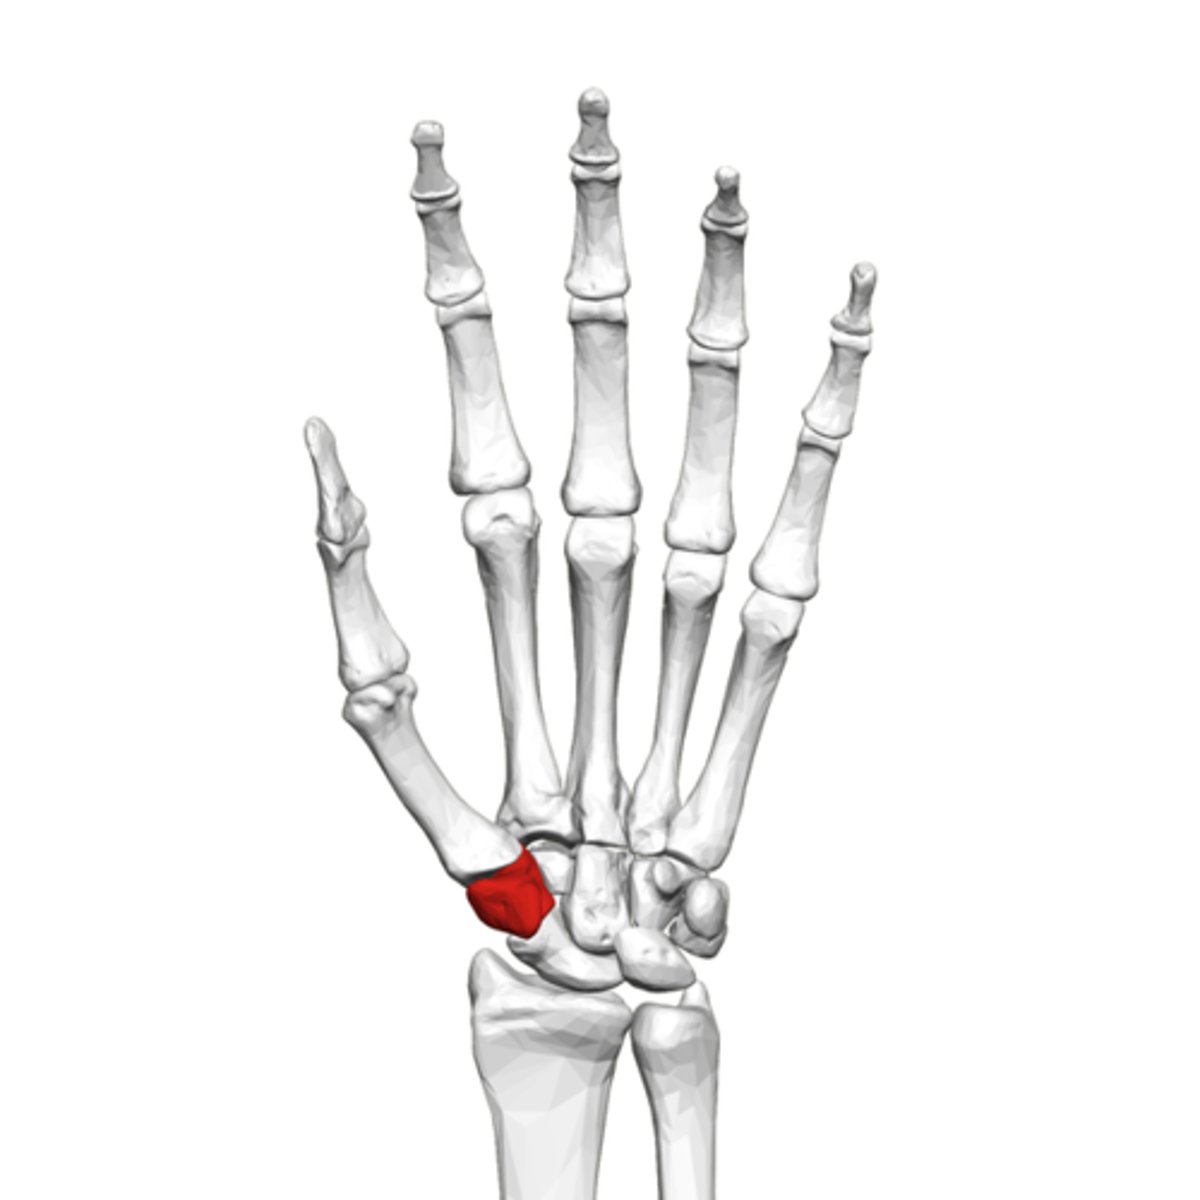

What is the term of the bones highlighted in red?

Trapezium